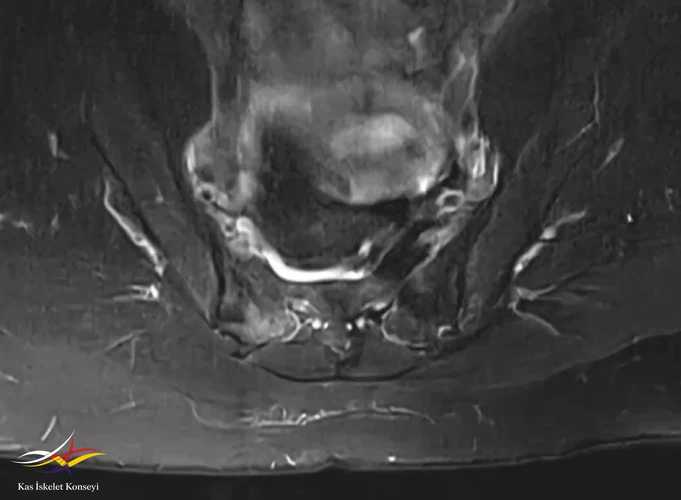

Resim 4. Sakroiliak MRG aksiyal kesitte sakrum sağında belirgin hiperintens alan.

Sakroileit düşünülmedi. Travmatik olabileceği veya doğum sonrası olabileceği düşünülen hasta takip ve kontrol MR önerildi.